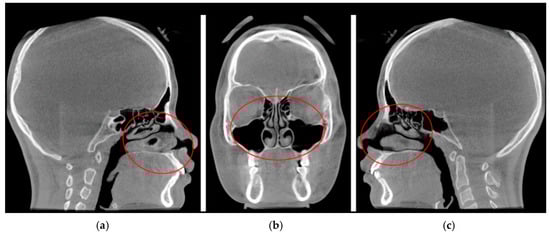

CBCT Volumetric Changes in Combined Nasal Cavity and Paranasal Sinuses Following RAMPA-ROA Therapy: A Retrospective Cohort Study with Reference to Longitudinal Growth Data

J. Clin. Med. 2026, 15(7), 2605; https://doi.org/10.3390/jcm15072605 (registering DOI) - 29 Mar 2026

Background: The interrelationship between craniofacial morphology and respiratory function is a central focus of orthodontic and dentofacial orthopedic research. This study aimed to evaluate the volumetric changes in the sinonasal complex (combined nasal cavity and paranasal sinuses) following Right Angle Maxillary Protraction Appliance

Background: The interrelationship between craniofacial morphology and respiratory function is a central focus of orthodontic and dentofacial orthopedic research. This study aimed to evaluate the volumetric changes in the sinonasal complex (combined nasal cavity and paranasal sinuses) following Right Angle Maxillary Protraction Appliance (RAMPA) therapy using cone-beam computed tomography (CBCT) and to compare these outcomes with established longitudinal growth benchmarks. Methods: A retrospective cohort analysis was conducted on 60 pediatric patients (24 males, 36 females; mean age: 86.60 ± 24.22 months) with radiologically clear paranasal sinuses at baseline (T1). Participants underwent RAMPA therapy for an average of 8.38 months. Volumetric quantification of the entire sinonasal complex—including the nasal cavity and all four paranasal sinuses (maxillary, ethmoid, sphenoid, and frontal)—was performed to ensure methodological alignment with existing normative growth data. Results: Total sinonasal volume increased significantly from 27,741.63 ± 10,675.85 mm3 at T1 to 32,248.00 ± 10,084.07 mm3 at T2 (p < 0.001), representing a mean gain of 4506.37 mm3 (16.24%). Notably, the annualized growth velocity under RAMPA therapy (6453 mm3/year) exceeded the physiological increment of age-matched normative data (~5418 mm3/year) by approximately 1.2 times. Despite a constricted baseline at T1 compared to normative values, the treatment group demonstrated a rapid “catch-up” growth trajectory. Conclusions: RAMPA therapy induces rapid and significant volumetric expansion of the sinonasal complex in pediatric patients, demonstrating a potent “acceleration effect” that surpasses natural physiological maturation. These findings suggest that orthopedic midfacial remodeling can effectively restructure the upper respiratory environment, bridging the gap between pathological constriction and normative developmental benchmarks in patients with maxillary hypoplasia.